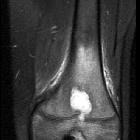

MRI

The “penumbra sign” on magnetic resonance (MR) imaging is useful for discriminating subacute osteomyelitis from other bone lesions. The penumbra sign is a rim lining of an abscess cavity with higher signal intensity than that of the main abscess on T1-weighted images with strongly and rapidly enhance after contrast.